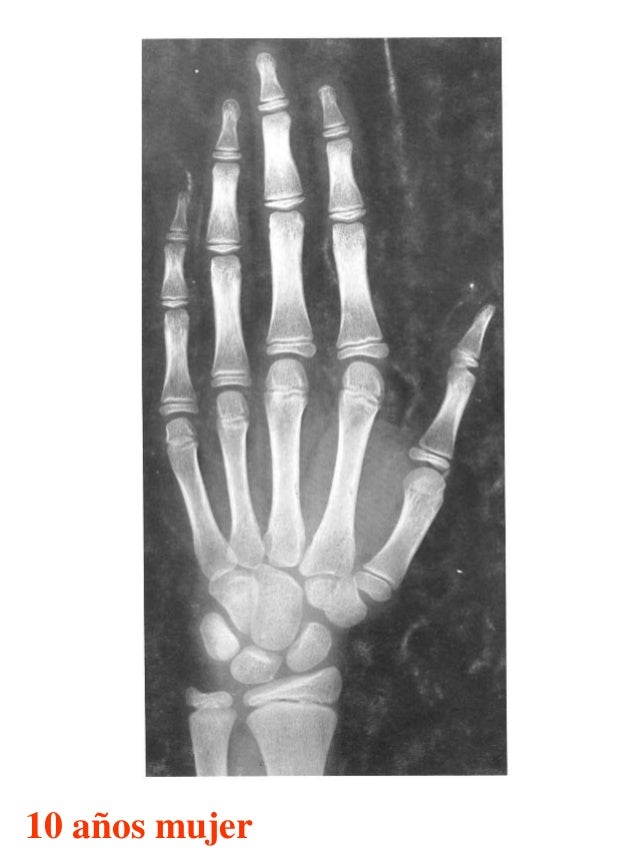

Figura 2 Imágenes de radiografías de mano y muñeca izquierda del

Figura 2 Imágenes de radiografías de mano y muñeca izquierda del Tablas De Greulich Y Pyle Edad Osea The greulich and pyle atlas is used to estimate the age of children and adolescents. El método de greulich y pyle(1) es un método simple de valoración de la edad ósea en pacientes pediátricos. El diagnóstico y la clasificación se basan en el examen físico, el análisis del crecimiento, la maduración ósea, la ecografía de útero y gónadas, y los. Tablas De Greulich Y Pyle Edad Osea.